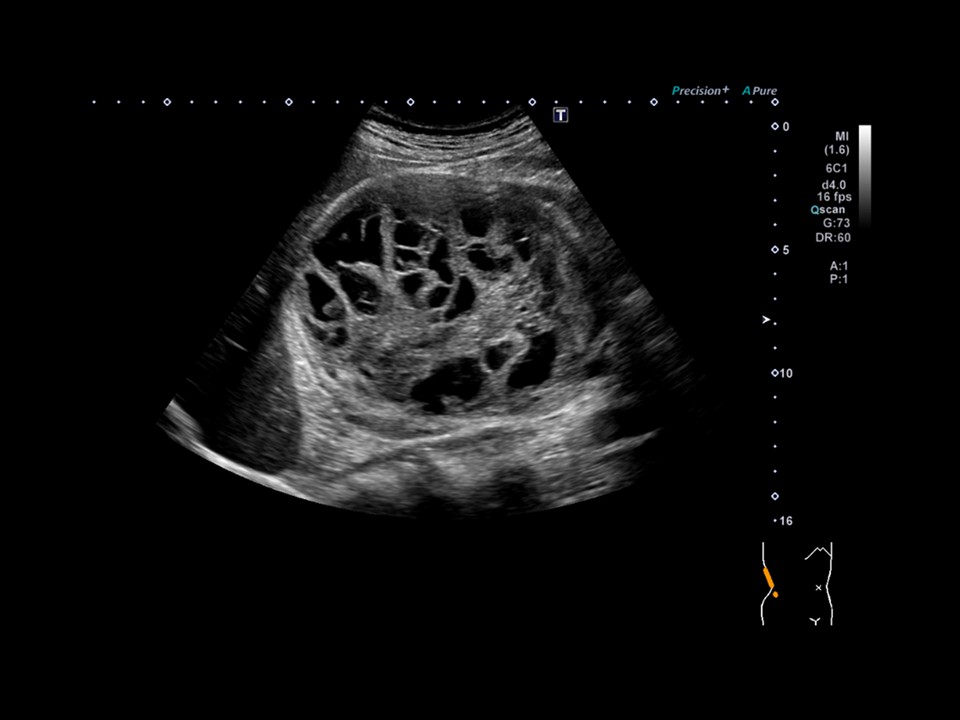

最優秀賞

片山 和弥 九段坂病院 放射線科

診断名SPN(充実性偽乳頭状腫瘍)

患者:20歳代 女性

使用機種:

Canon Xario 200

周波数:3.8 MHzコメント(術者の一言)

あえてスペックの低い機器で記録しました。条件設定しだいで、ここまで綺麗に腫瘤内部の充実部分と嚢胞状の混在が描出出来ました